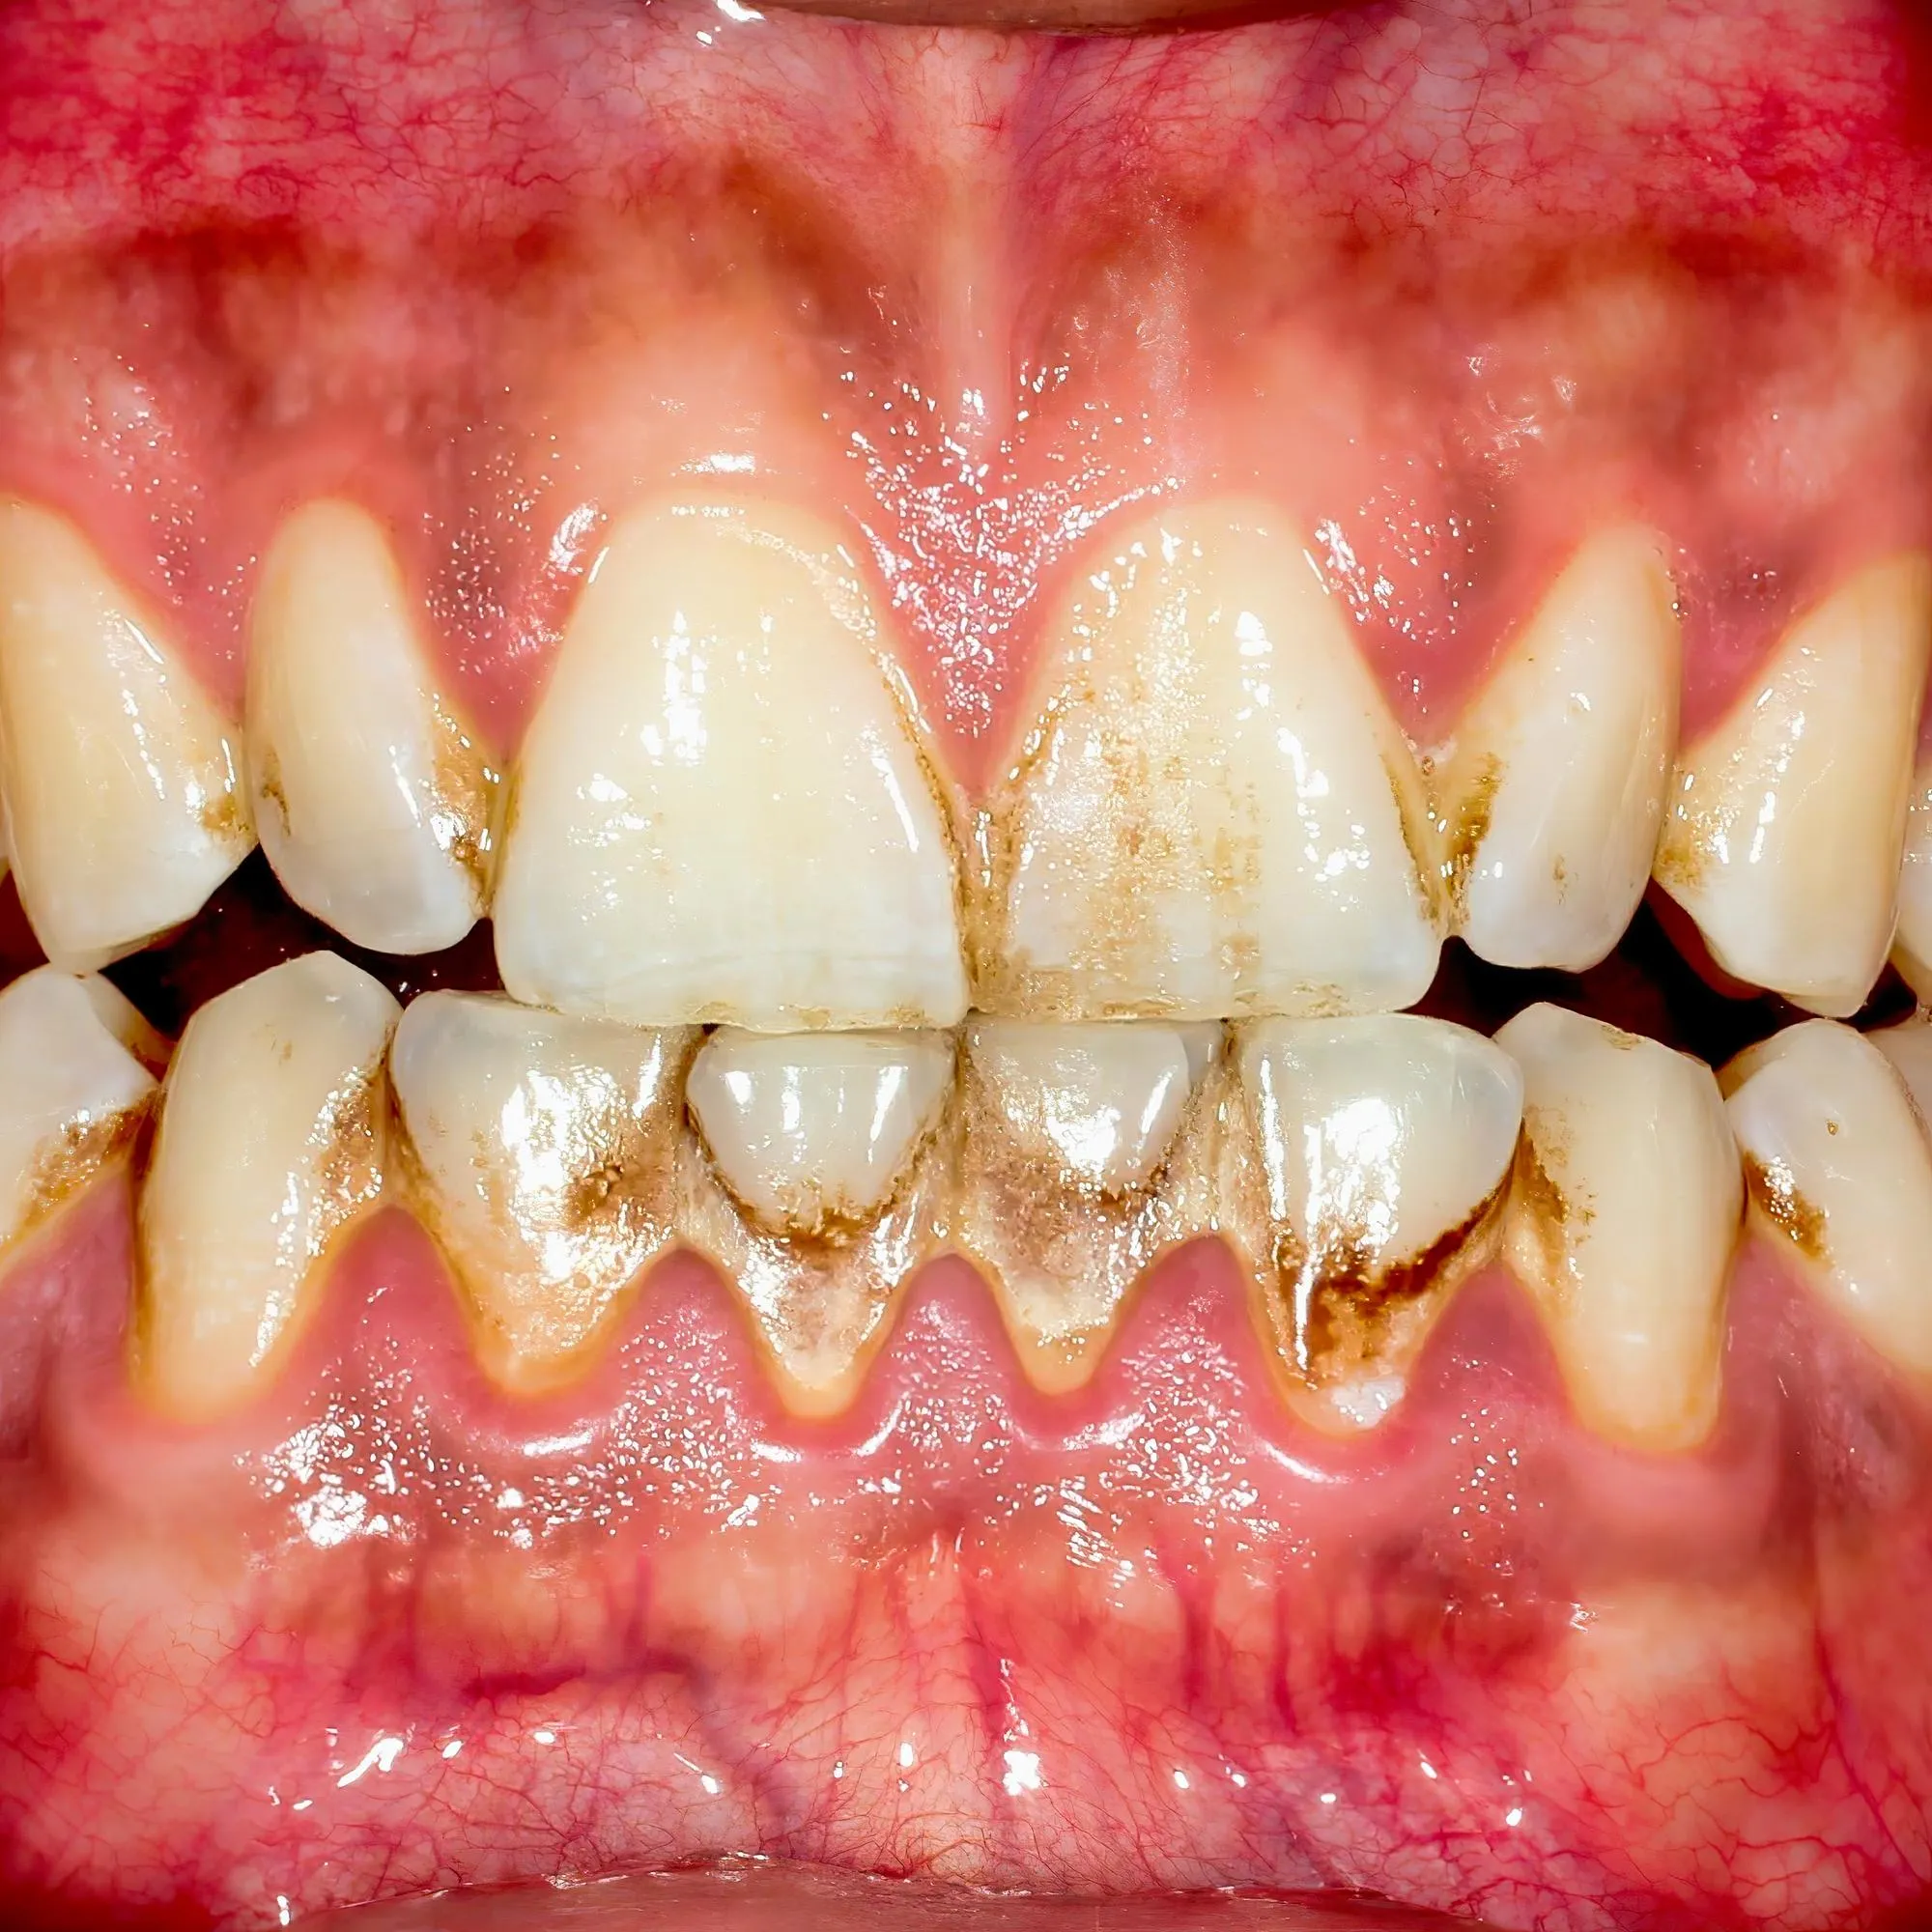

Gum problems don’t just appear out of nowhere. Usually, it starts small. Maybe you ignore a tiny bleed. Then it gets worse.

• Gingivitis : Red, swollen gums. Bleeding during brushing.

• Periodontitis: When infection spreads deeper.

• Gum Recession: Gums pulling away. Teeth look longer.

• Abscesses: Painful pus pockets in gums.

Each one’s a story of neglect. Left untreated, they spiral into serious issues. This is where gum treatment and surgeries step in. Fixing problems before they ruin your smile.